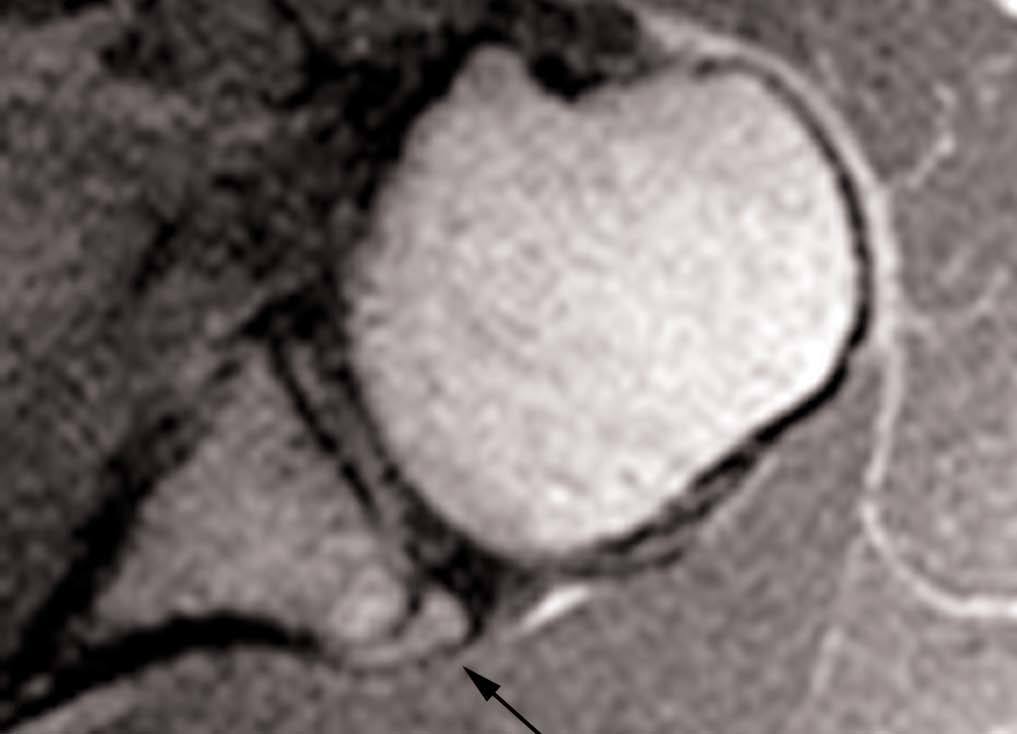

Esta lesión se produce a consecuencia de una tracción repetitiva de la unión cápsulo-perióstica posterior, produciéndose una osificación semejante a un espolón óseo (fig. 15).

Fig. 15.--Lesión de Bennett. Tomografía axial computarizada (TAC) axial (A) y resonancia magnética (RM) T1 axial (B) que revelan la presencia de un «espolón» óseo adyacente al borde glenoideo posterior (flechas en A y B). Nótese la ausencia de una lesión del labio glenoideo posterior en B.